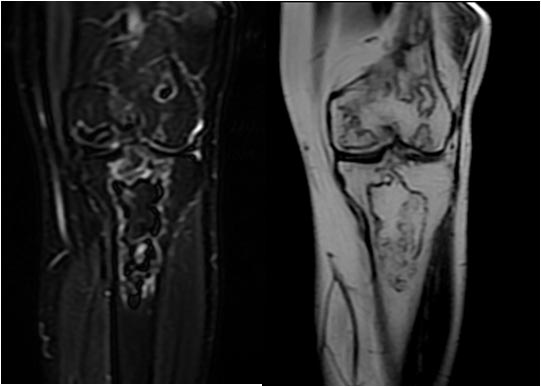

Otro ejemplo en un paciente con infartos óseos múltiples en fémur distal y tibia proximal.